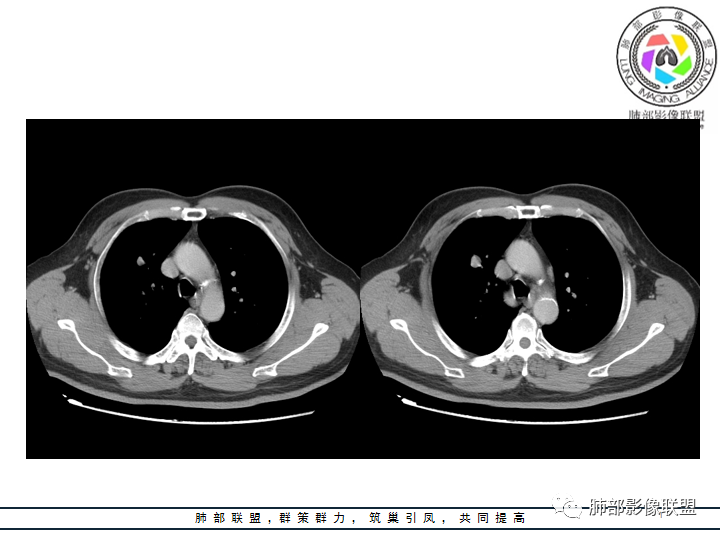

老年男性患者,长期吸烟史,没有呼吸系统临床表现。胸部CT示右肺上叶实性密度结节影,密度均匀,未见空洞及钙化,边缘较光整,未见分叶及毛刺。血管影旁现侧出,支气管进入并截断,不均匀强化。

刘莲凤:病灶周围圆钝!血管边上走!支持良性,PSP,鉴别错构。

万琦:看到有强化,错构瘤可能性小,感觉分支支气管有截断,大细胞需要考虑一下,类癌>PSP>大细胞,男性类癌发生率比较低。

洪桥爱:我觉得支气管贴边擦过,支气管挂果,考虑错构瘤;鉴别血管周瘤:似见肺动脉穿过。